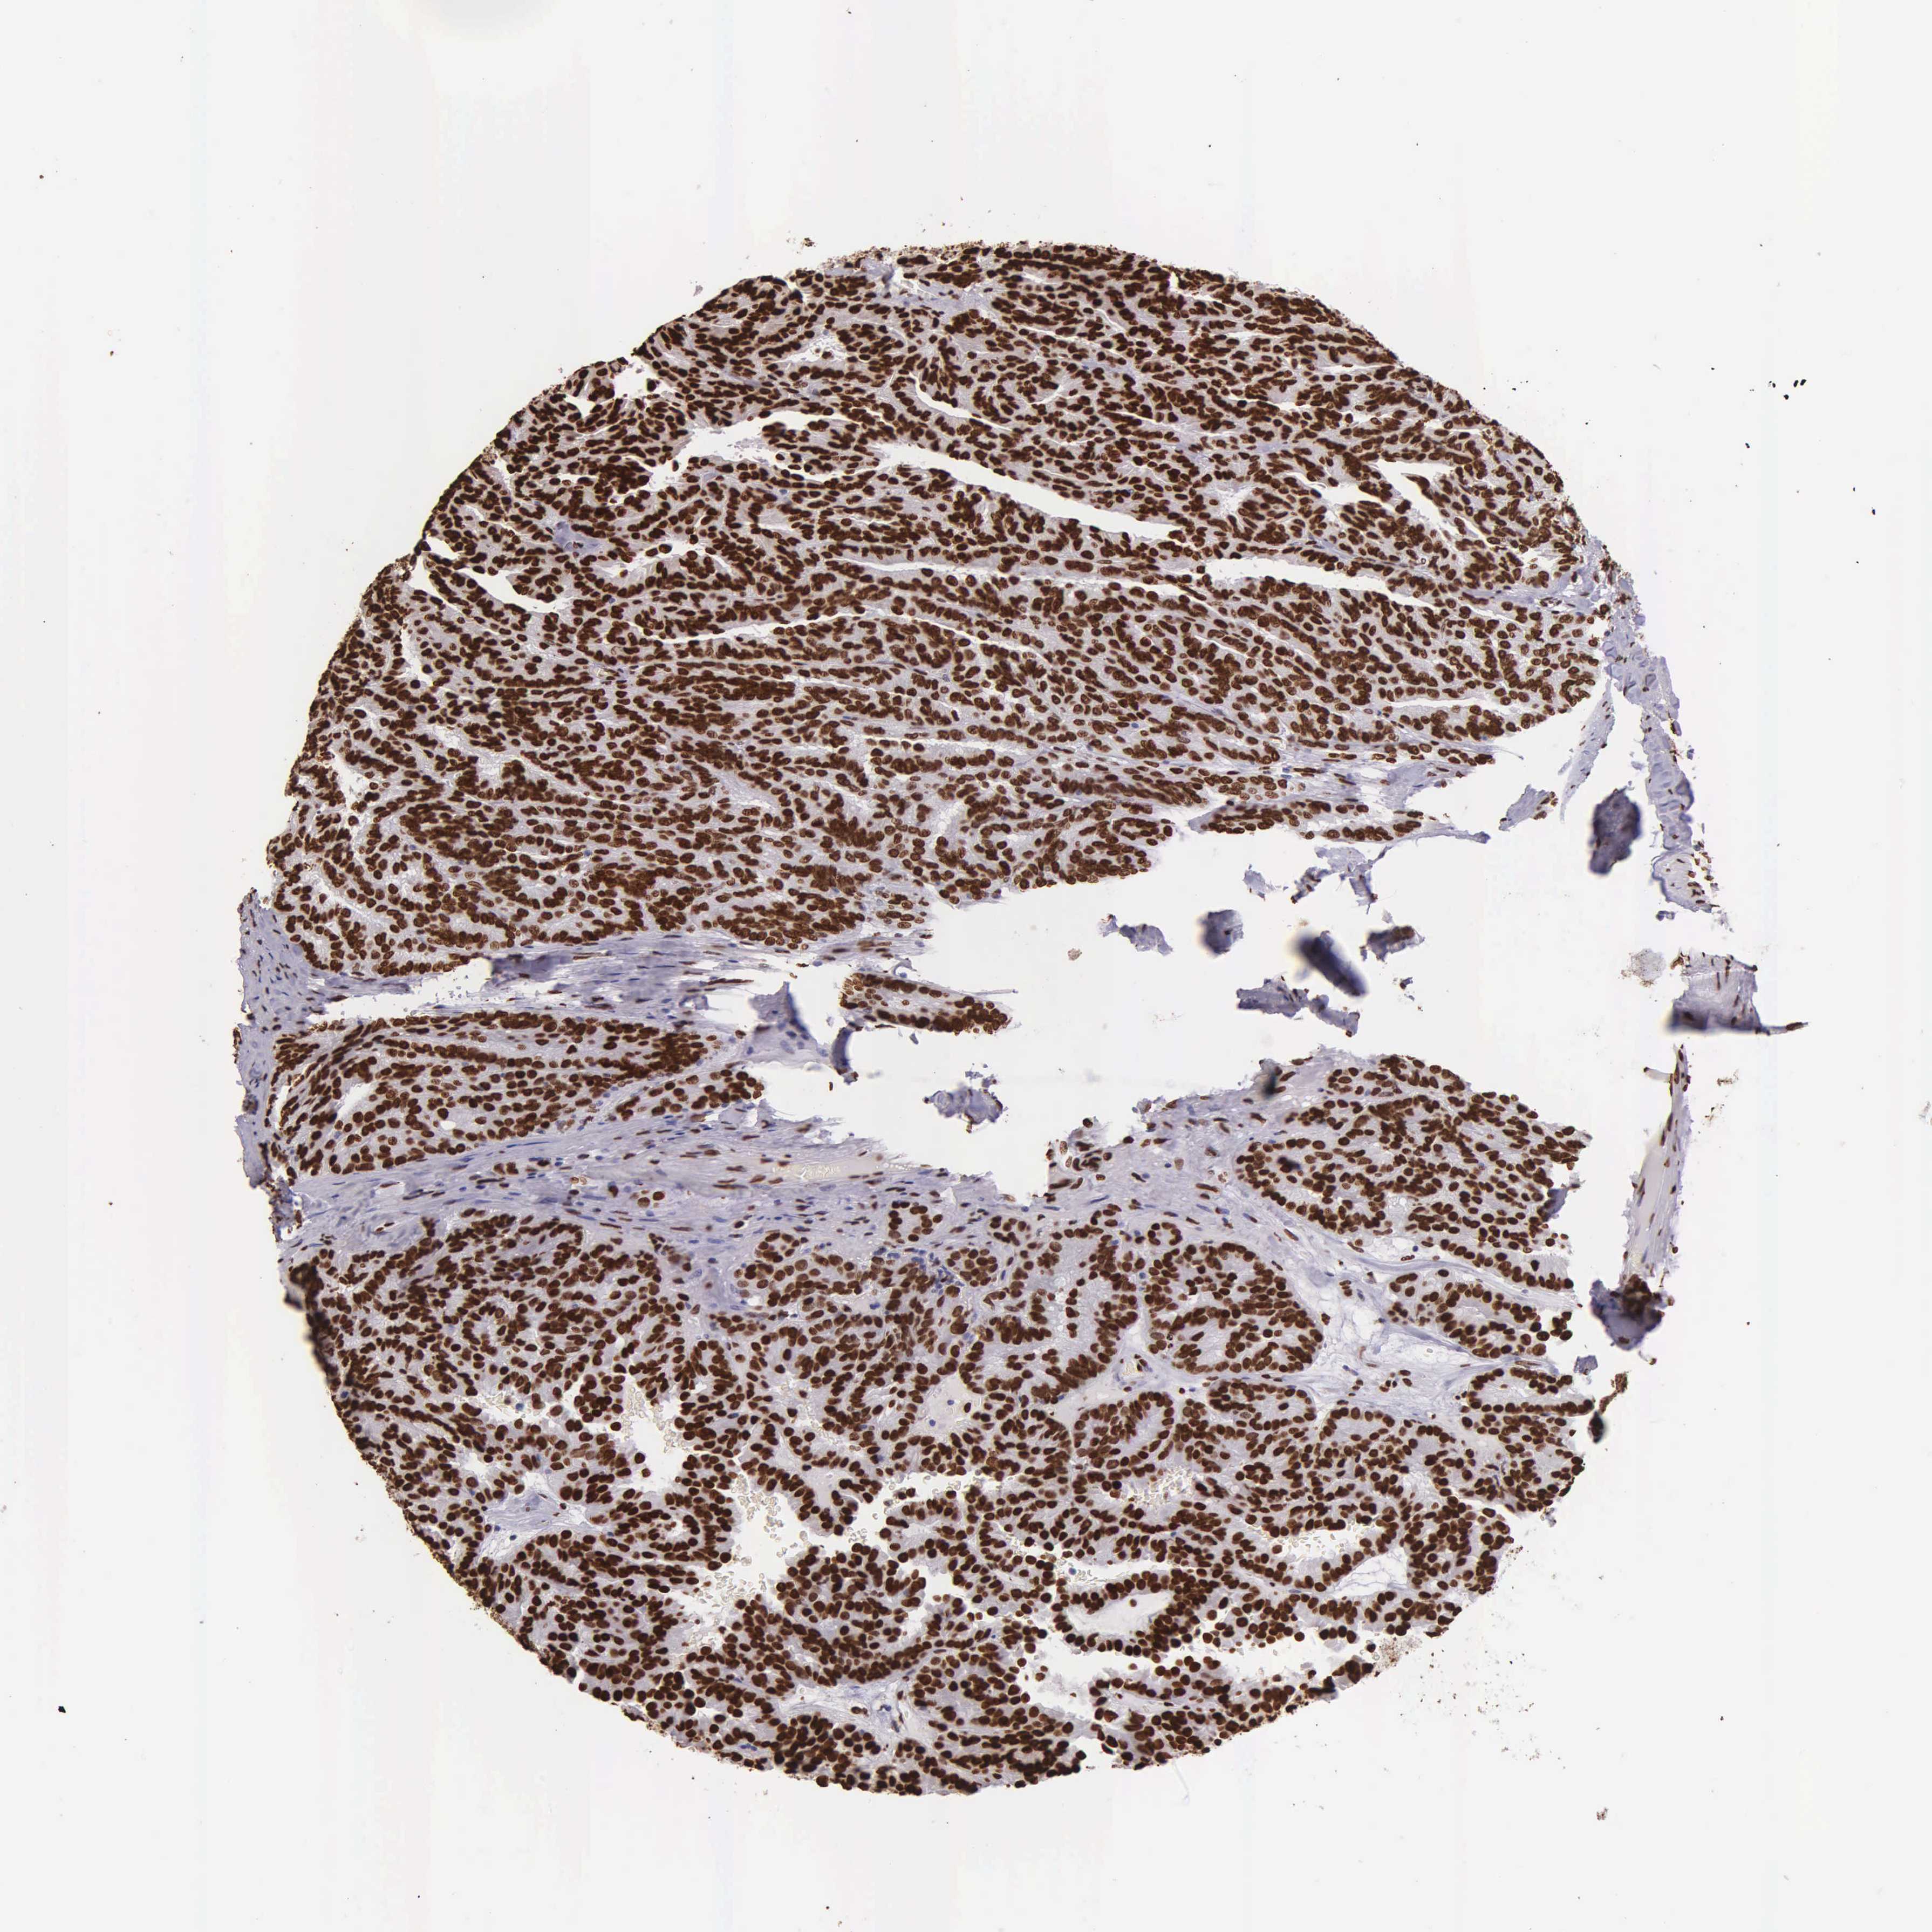

KIDNEY RENAL CLEAR CELL CARCINOMA (TCGA) - Interactive survival scatter ploti

The Survival Scatter plot shows the clinical status (i.e. dead or alive) for all individuals in the patient cohort, based on the same data that underlies the corresponding Kaplan-Meier plots. Patients that are alive at last time for follow-up are shown in blue and patients who have died during the study are shown in red.

The x-axis shows the expression levels (FPKM) of the investigated gene in the tumor tissue at the time of diagnosis. The y-axis shows the follow-up time after diagnosis (years). Both axes are complimented with kernel density curves demonstrating the data density over the axes. The top density plot shows the expression levels (FPKM) distribution among dead (red) and alive patients (blue). The right density plot shows the data density of the survived years of dead patients with high and low expression levels respectively, stratified using the cutoff indicated by the vertical dashed line through the Survival Scatter plot. This cutoff is automatically defined based on the FPKM cutoff that minimizes the p-score. The cutoff can be changed by dragging the vertical line or by entering a cutoff value in the square labeled "Current cut-off".

Under the Survival Scatter plot the p-score landscape (black curve; left axis) is shown together with dead median separation (red curve; right axis). Dead median separation is the difference in median mRNA expression between patients who have died with high and low expression, respectively. It is calculated as follows: median FPKM expression of dead patients with high expression - median FPKM expression of dead patients with low expression. This is intended to aid the user in visually exploring custom cutoffs and the associated p-scores and dead median separation.

Individual patient data is displayed and can be filtered by clicking on one or more of the category buttons on the top of the page. Categories describing expression level and patient information include: high, low, alive, dead, female, male and tumor stages. The scale of the x-axis can be toggled between linear and log-scale by clicking on the "x log" button. Mouse-over function shows TCGA ID, patient information and mRNA expression (FPKM) for each patient.

& Survival analysisi

Kaplan-Meier plots summarize results from analysis of correlation between mRNA expression level and patient survival. Patients were divided based on level of expression into one of the two groups "low" (under cut off) or "high" (over cut off). X-axis shows time for survival (years) and y-axis shows the probability of survival, where 1.0 corresponds to 100 percent.

H1-0 is not prognostic in Kidney Renal Clear Cell Carcinoma (TCGA)

Best expression cut offi

Based on the FPKM value of each gene, patients were classified into two groups and association between prognosis (survival) and gene expression (FPKM) was examined. The best expression cut-off refers the FPKM value that yields maximal difference with regard to survival between the two groups at the lowest log-rank P-value. Best expression cut-off was selected based on survival analysis .

When clicking on this number, the vertical dashed line indicating cut-off, the interactive survival plot, and the Kaplan-Meier curve will be adjusted to show results based on the best expression cut-off.

: 71.87

P scorei

Log-rank P value for Kaplan-Meier plot showing results from analysis of correlation between mRNA expression level and patient survival.

N/A

Average pTPM 71.5

Number of samples 521